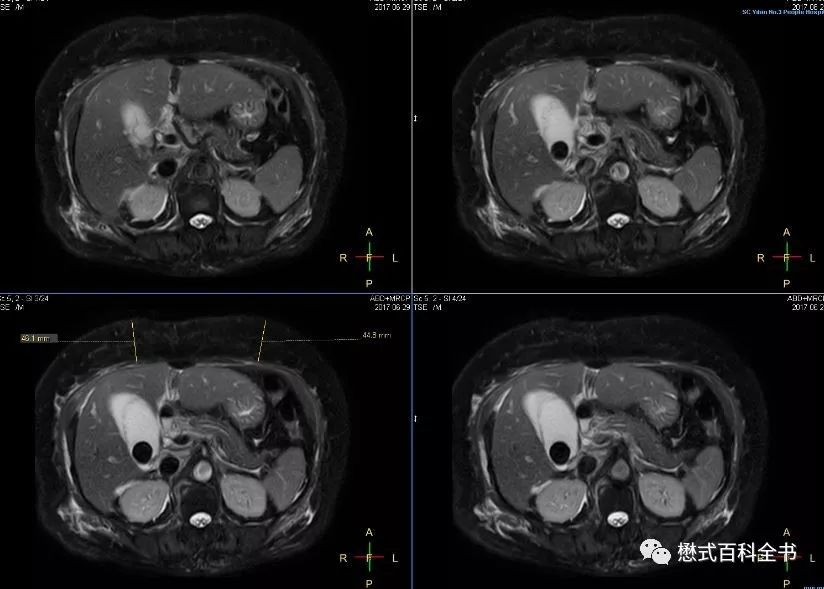

图27:胰头区囊性占位,肝内胆管、胰管扩张(Ingenia 1.5T图像)

有的时候,如果要诊断胆囊结石或者胆管结石,相对难度不大。明显的结石,经常在常规的横轴位T2WI或者冠状位T2WI上即可显示。难度大的在于胆总管下段的占位或者不确定的梗阻。

图28:横轴位显示明显的胆囊结石